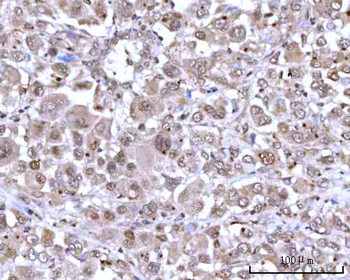

IHC staining of FFPE human lymph node with CD72 antibody (clone BU40). HIER: boil tissue sections in pH9 10mM Tris with 1mM EDTA for 20 min and allow to cool before testing.

IHC staining of FFPE human lymph node with CD72 antibody (clone BU40). HIER: boil tissue sections in pH9 10mM Tris with 1mM EDTA for 20 min and allow to cool before testing.